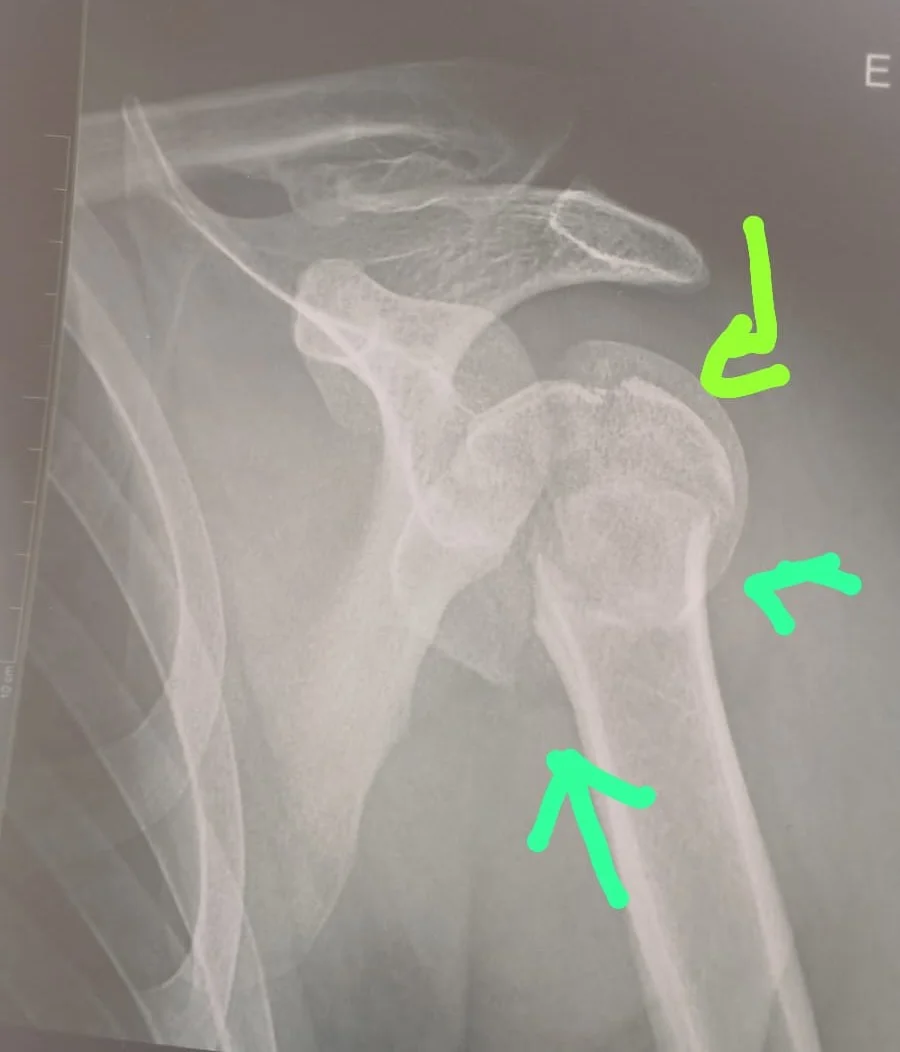

De acordo com documentos médicos apresentados, Clerio necessita realizar com urgência uma osteossíntese de fratura de úmero proximal, procedimento indicado para realinhar e fixar os fragmentos ósseos do ombro. Com a demora, o quadro clínico se agravou.

Na rede particular, o procedimento foi avaliado em cerca de R$ 137.800,00, valor que inclui honorários médicos, materiais hospitalares e acompanhamento pós-operatório — quantia impossível para a família custear. A espera já provoca consequências mais graves: o jovem pode precisar de prótese e corre risco de perder os movimentos do braço.